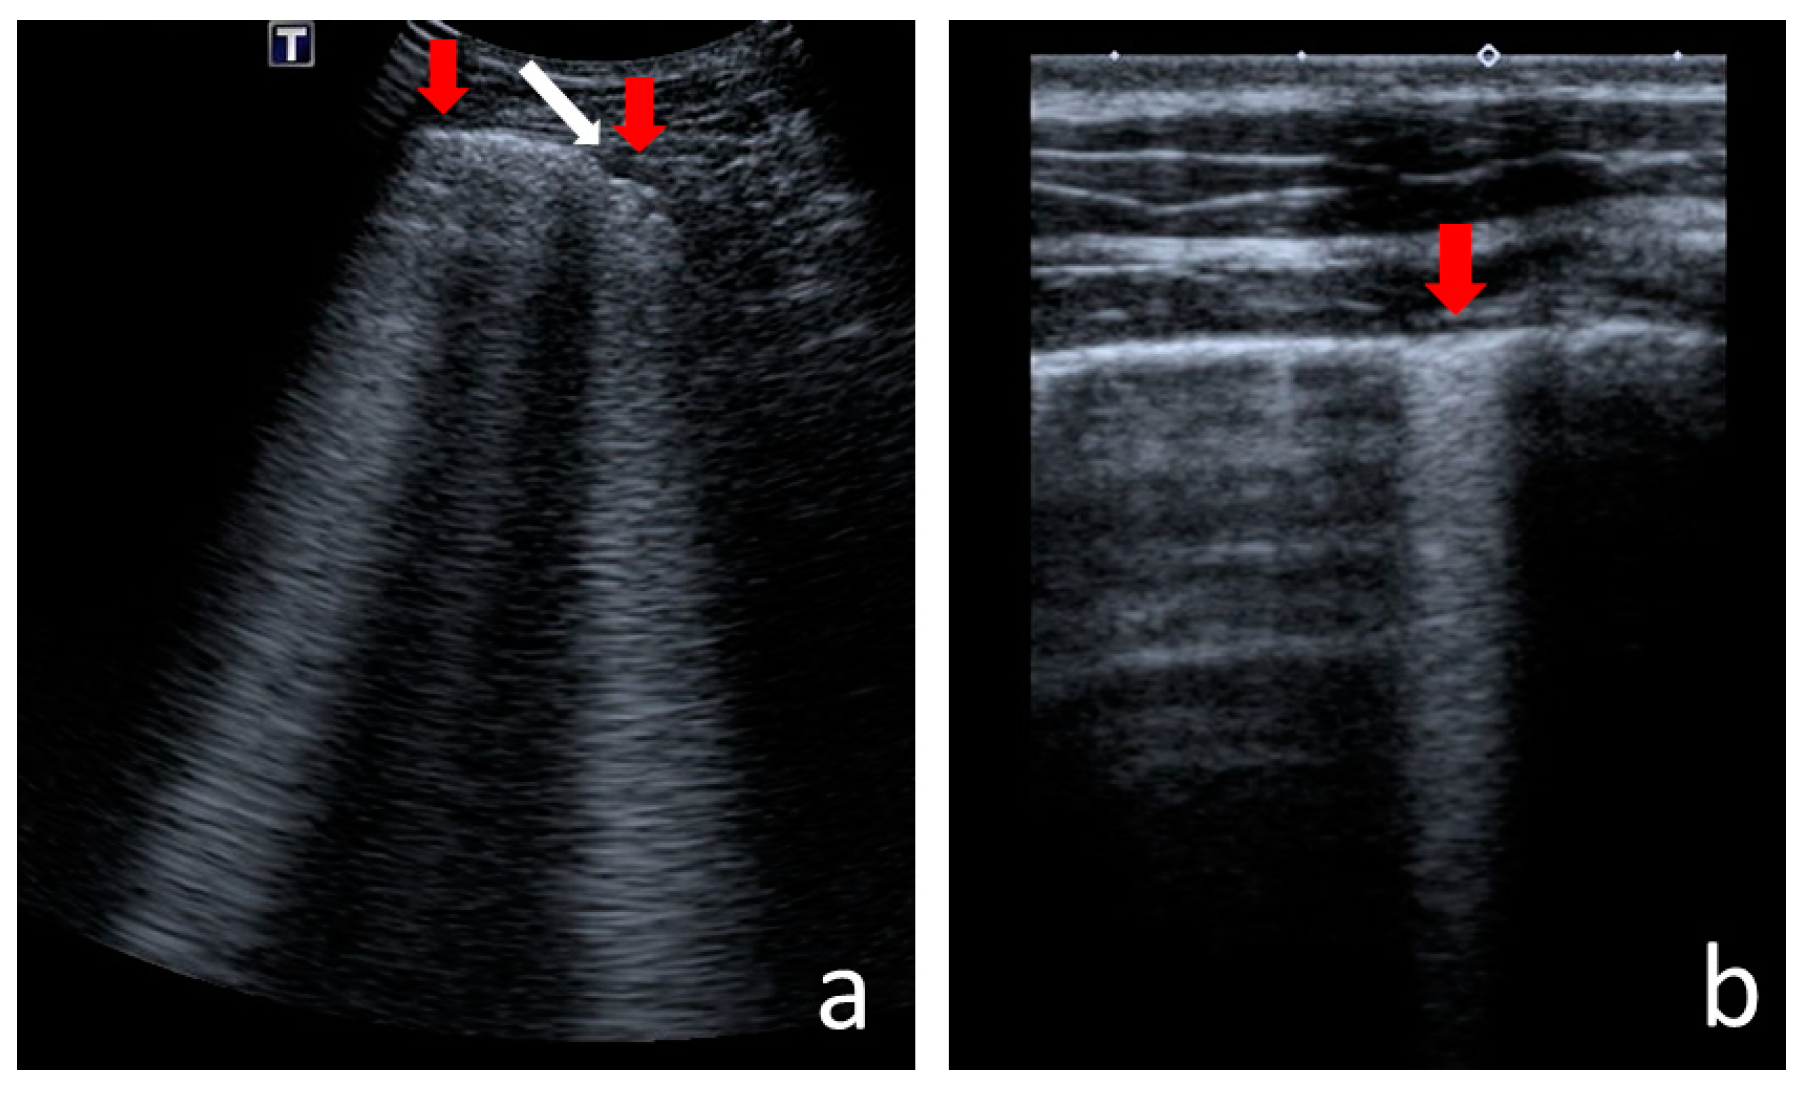

- Consolidations—hypoechoic, tissue-like areas: (a) small (≤10 mm) (Figure 6), and (b) major (>10 mm) (Figure 7); usually, major consolidations have the following associated features: the loss of pleural line echogenicity over the area of consolidation, absence of A-lines, presence of dynamic or static air bronchogram/air trapping and vascular pattern (in CD option) within the area, C-lines below the area, B-lines surrounding it [17,31];